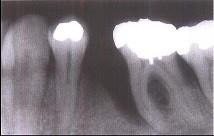

问题 牙槽骨垂直型吸收的特点,除外()

选项 A.牙槽骨不发生水平方向的吸收 B.牙槽骨发生垂直或斜型方向的吸收 C.与牙根面形成角型的骨缺损 D.牙槽嵴高度降低不多,而牙根周围的骨吸收较多 E.垂直吸收多形成骨下袋

答案 A